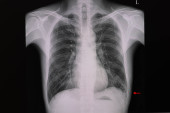

RTG klatki piersiowej pacjenta po lewej torakotomii płuc (chirurgiczne usunięcie płuca). Pacjent ma również złamane prawe żebro..

Zdjęcie "RTG klatki piersiowej pacjenta po lewej torakotomii płuc (chirurgiczne usunięcie płuca). Pacjent ma również złamane prawe żebro.." może być wykorzystywane do celów osobistych i komercyjnych zgodnie z warunkami zakupionej licencji Royalty-free. Obraz jest dostępny do pobrania w jakości wysokiej rozdzielczości do 5760x3840.